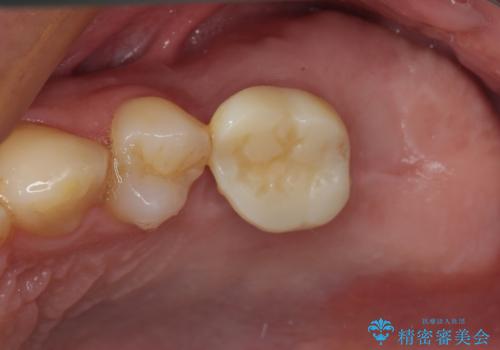

- 奥歯のむし歯と放置したむし歯を気にして来院された患者様です。

奥の歯は抜歯が必要なため、インプラント埋入による補綴治療を行うこととしました。

手前の歯は状態は良くないものの、抜歯するほどではないと判断したため、根管治療後にオールセラミッククラウンにて補綴治療を行うこととしました。